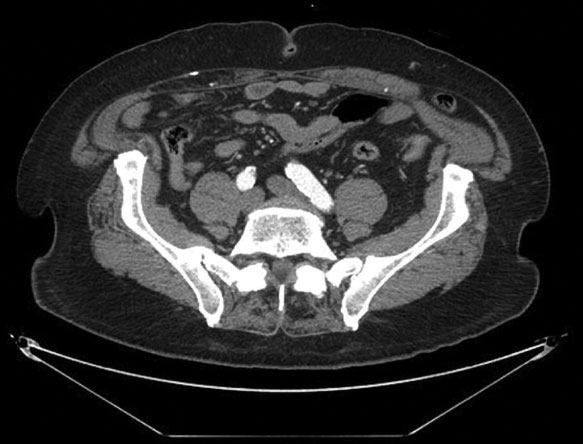

A CT scan of the abdomen and pelvis, however, remains a more useful diagnostic modality.4 This test provides an accurate view of the anterior abdominal wall structures. It is also highly sensitive for detecting intra-abdominal mass lesions in this area.

In Figure 4, notice the colon, marked by the arrow, as it passes through the Spigelian fascia just lateral to the left rectus muscle and becomes entrapped below the external oblique fascia. More inferiorly on the CT scan, in Figure 5, the internal oblique and transversus abdominis muscles can also be seen deep to the hernia, near the iliac crest.